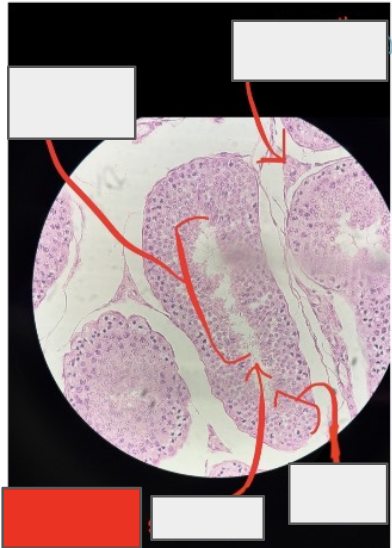

testes

What organ is this?

Seminiferous tubules

Leydig (interstitial endocrine) cells

Spermatogenic cells

Spermatozoon